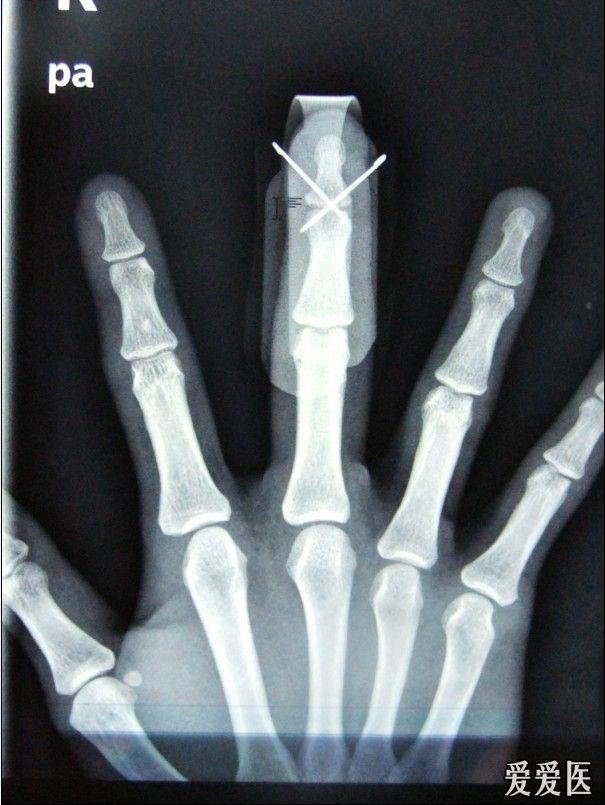

手指骨折手术两根克氏针固定后的疑问(有x片) - 骨

指骨骨折克氏针内固定一例

环指骨折克氏针固定一例